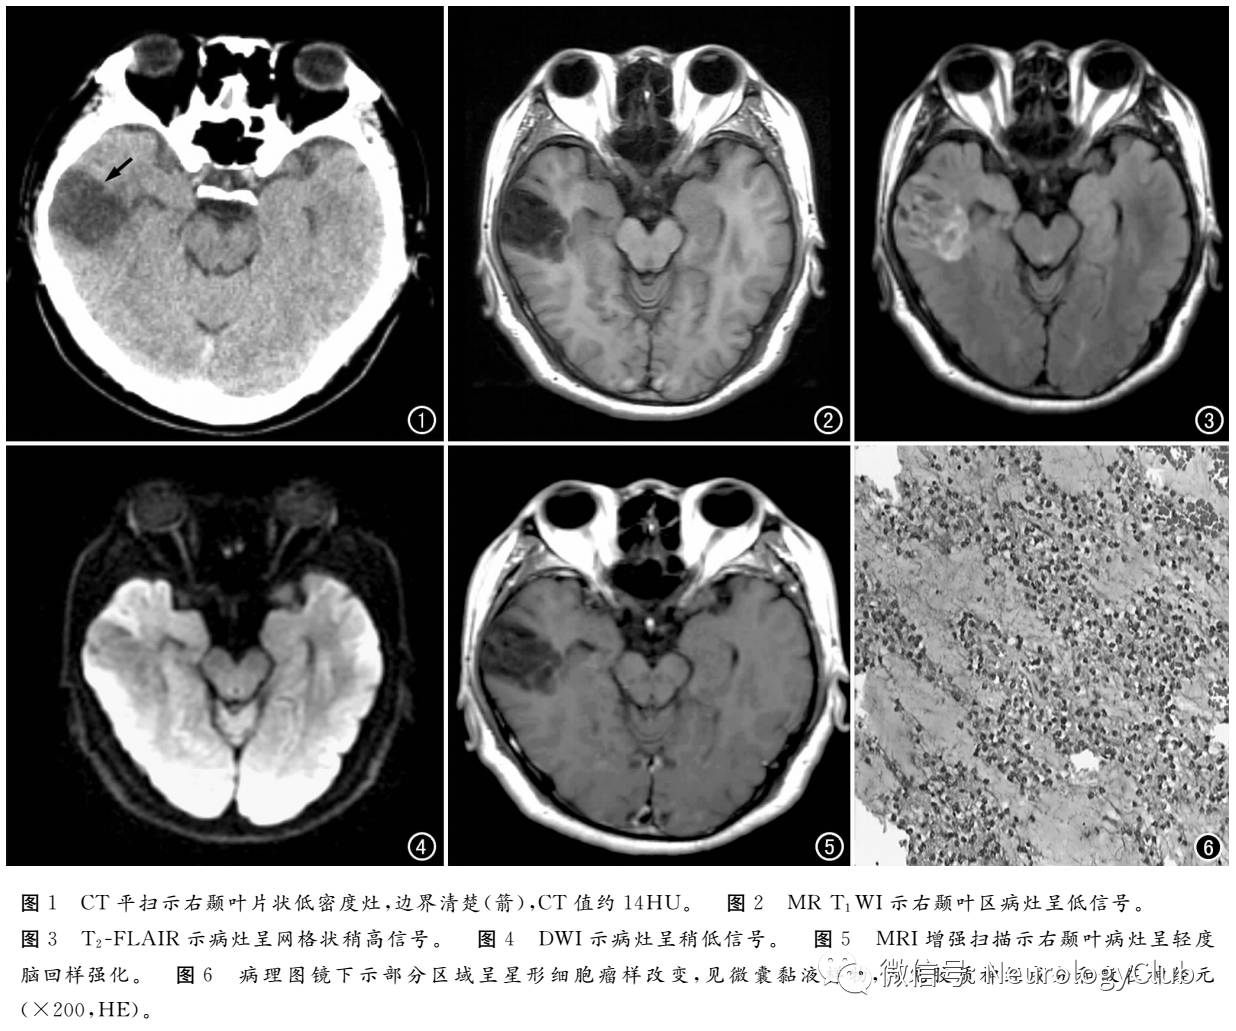

1年前CT检查:右颞叶见大小约30mm×24mm片状低密度影,边界清楚,CT值约14HU,无明显占位效应(图1)。诊断:右颞叶软化灶。

MRI检查:平扫示右颞叶有团片状长T1、长T2信号,T2/FLAIR图像上呈网格状稍高信号,DWI上呈稍低信号,无明显占位效应(图2-4),增强扫描示右颞叶病灶轻度脑回样强化(图5)。诊断:右颞叶缺血性病变。

病理诊断:送检标本(致痫灶)为灰白色组织,大小约6cm×3.5cm×1.8cm,切面有出血、胶冻样;镜下示部分呈星形细胞瘤样改变,可见微囊粘液样物,其内见胶质神经成分及散在神经元;(海马区)见胶质细胞及神经元。 免疫组化染色结果:S-100阳性,GFAP阴性;嗜银,阴性;Ki-67增生指数<1%,Syn阳性。诊断:符合(右颞叶及内侧)胚胎发育不良性神经上皮肿瘤。